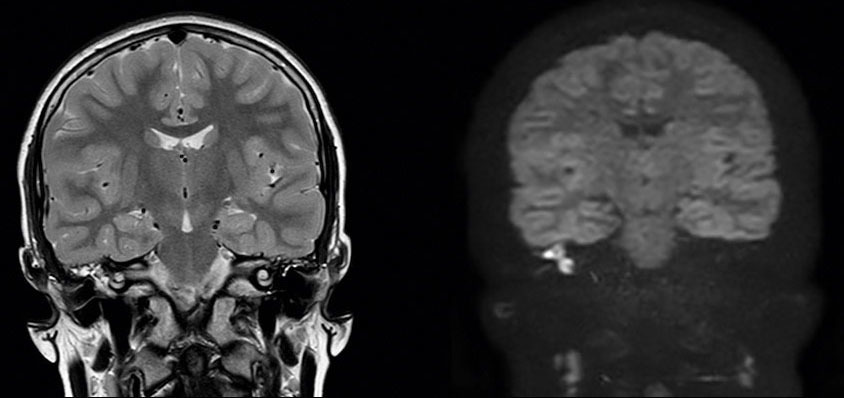

Devant ces atteintes multiples, vous demandez un scanner et une imagerie par résonance magnétique (IRM) en urgence qui sont représentés ci-dessous.

Question 11 : Qu’en pensez-vous ?

Question difficile, à laquelle on peut (et doit) répondre avec la clinique. En effet, le canal est ouvert sur le scanner (en coupe coronale sur la figure 4), mais surtout on peut le déduire devant le fait que le patient a un nystagmus avec un cholestéatome

La cavité de l’oreille est noire : donc il y a de l’air. Elle n’est pas comblée par du tissu

Faux, le scanner montre un comblement aspécifique, sans différencier tissu, liquide ou fibrose

Avec la séquence de diffusion à droite, qui est pathognomonique du cholestéatome

C’est une séquence de diffusion

L’IRM est le seul examen pathognomonique du cholestéatome. Le scanner montre la lyse osseuse mais n’est pas du tout spécifique de l’atteinte. Il n’est pas nécessaire de connaître les structures de l’oreille interne sur le scanner (qui sont très compliquées), mais il faut au moins reconnaître une oreille moyenne pleine (contenu gris) d’une oreille saine aérée (contenu en noir). On peut ensuite déduire de l’énoncé les destructions correspondantes. On aurait pu aussi dire dans cette question que le canal du nerf facial était détruit : c’est forcément le cas puisqu’il y a une atteinte du facial.